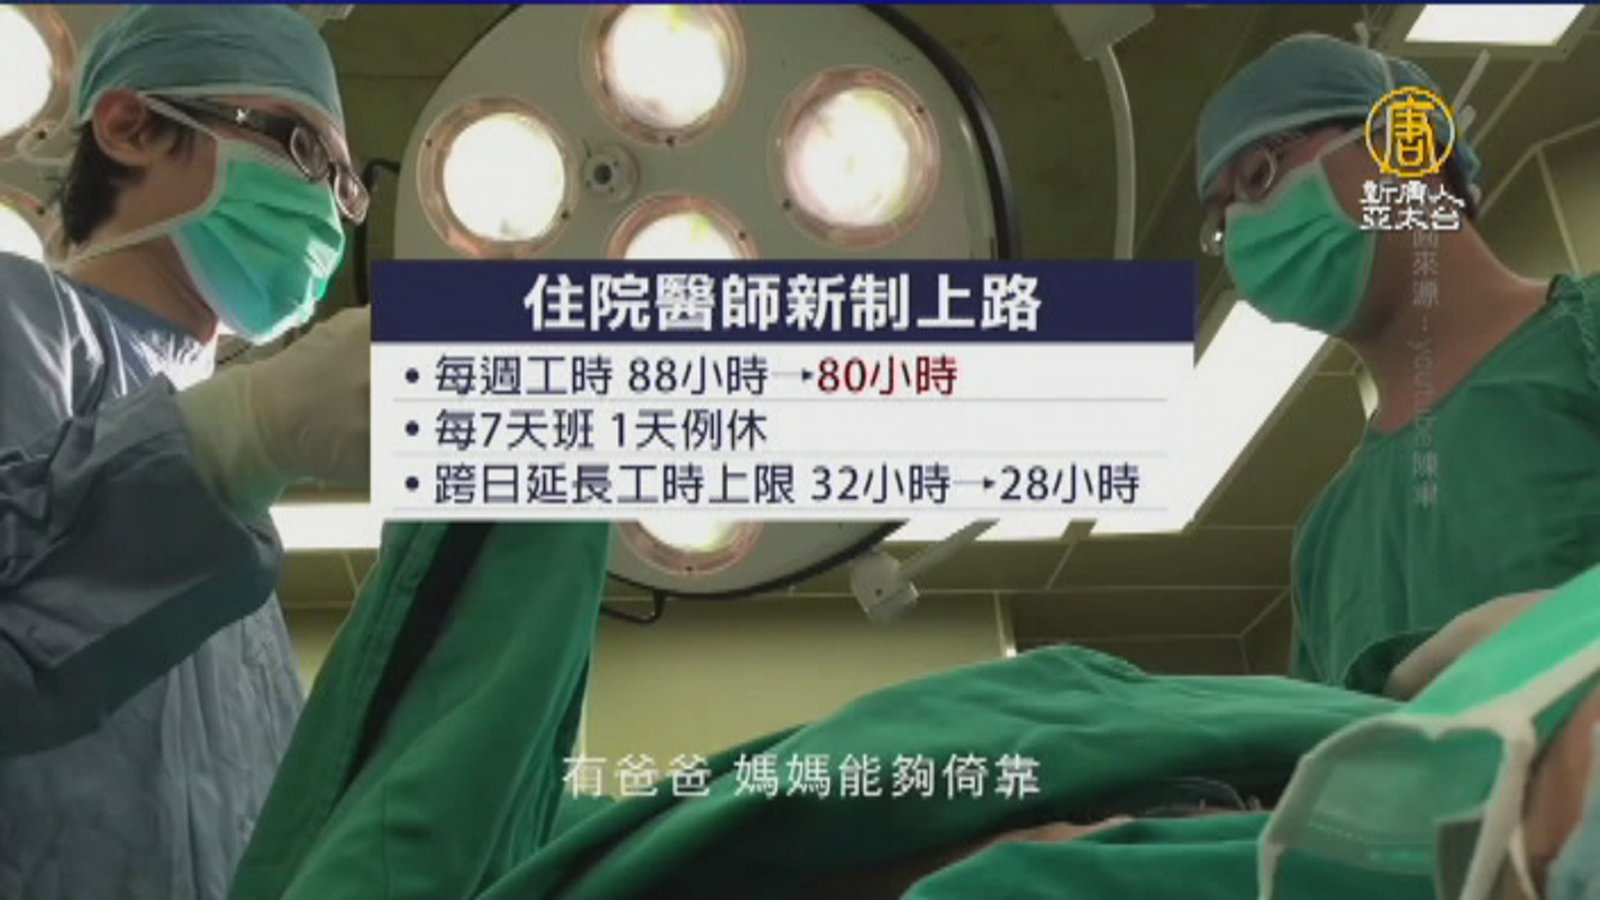

住院醫師每週工時縮8小時 手術量恐減少

2017-08-01 21:12:44住院醫師新制今天上路,每週工時從原本的88小時降為80小時,每上7天班,得有1天例休。不過現在醫界和民眾都憂心,這可能影響手術和看診排程,如果要維持現有水準,只能增聘住院醫師、或增加護理師彌補,成本又增加了。